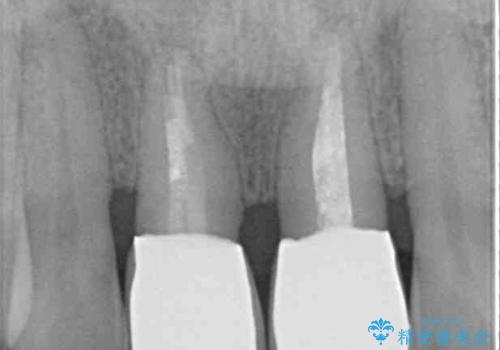

- 隙間の空いた前歯をセラミッククラウンで補隙したところ、歯肉から出血してしまい、何とかしたいとのことで来院された患者様です。

初めは前歯のみの処置で改善を希望されていたため、広範囲に処置範囲を広げることで歯の幅がバランスする治療を提案しましたが、削らなければならない歯が増えてしまうため、患者様と相談して全顎矯正により前歯のスペースを閉じていくこととしました。

不適合なクラウンが装着されていたため、歯周ポケットが深くなっていましたので、矯正治療前に歯周外科処置を行って歯周ポケットを除去し、矯正治療後にオールセラミッククラウンにて補綴治療を行うこととしました。